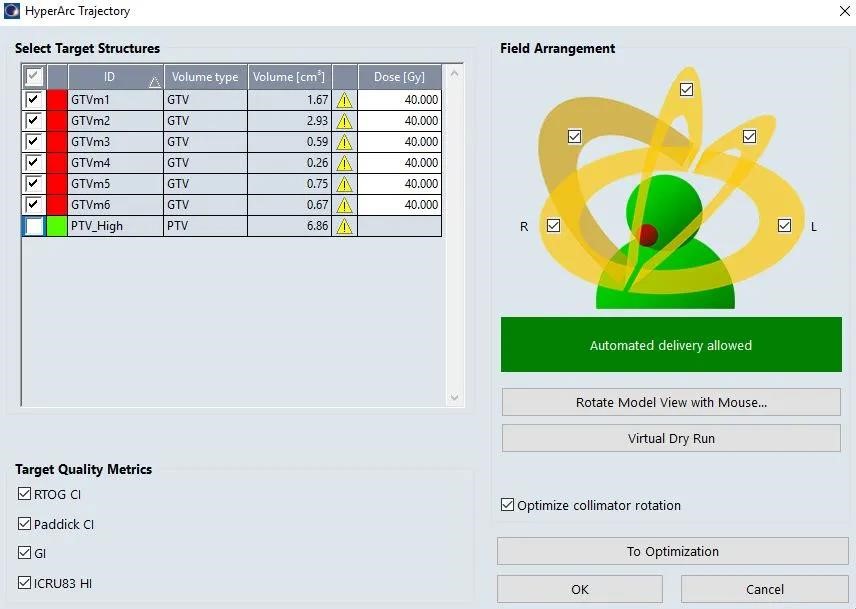

自动布野

1、TPS根据靶区位置形状自动定义等中心、自动布置非共面旋转弧形射野,物理师根据经验可适当调整

2、TPS可自动优化准直器角度,减少孤岛阻塞、提高治疗效率、降低正常脑组织剂量

3、TPS可用Virtual Dry Run功能进行可视化碰撞检测

优化

1、自动添加靶区Lower优化条件

2、ALDO (Automatic Lower Dose Objective)自动设置所有靶区都得到98%体积的覆盖,避免多靶点计划不同靶点剂量覆盖不一致

3、SRS NTO:靶区外剂量跌落更加快速